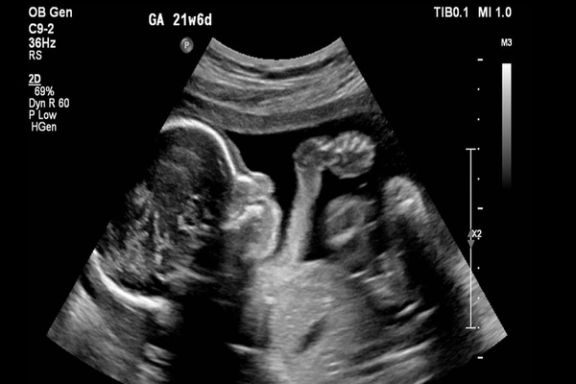

روزنامه شرق: در ایران از هر ۷۰۰ نوزاد یکی با سندروم داون به دنیا میآید

روزنامه شرق در گزارشی نوشت در ایران از هر ۷۰۰ تولد زنده، یک کودک با سندروم داون به دنیا میآید و اکنون جمعیت افراد با سندروم داون در ایران ۱۲۰ هزار نفر است.